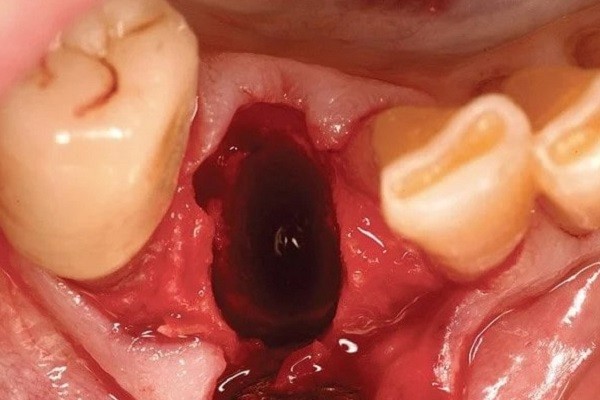

- Bước 4: Cầm máu và dặn dò: Sau khi răng được lấy ra, bác sĩ sẽ đặt gạc để cầm máu và hướng dẫn khách hàng các mẹo cầm máu sau khi nhổ răng hiệu quả, đồng thời hẹn lịch tái khám nếu cần thiết.

Trong thời gian hồi phục sau khi nhổ răng hàm trên trong cùng bị sâu, bạn cần theo dõi các dấu hiệu bất thường có thể là biểu hiện của biến chứng. Cảnh báo bao gồm:

- Chảy máu nhiều hoặc kéo dài hơn 24 giờ.